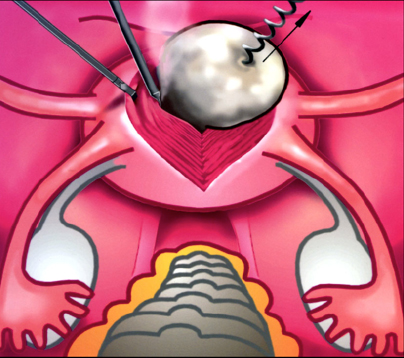

Современные методы лапаротомии и миомэктомии